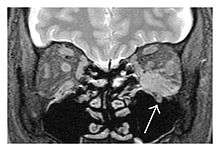

The extent of inflammation that can occur in IgG4-ROD is well demonstrated on magnetic resonance imaging (MRI).

![]() Swelling of the left superior and lateral rectus muscles, a mass lesion around the left optic disc (arrow), and enlargements of the left supraorbital nerve and the right infraorbital nerve (arrow heads) in a 60-year-old man with a serum IgG4 of 463 mg/dL.[1] (T1-weighted MRI) |